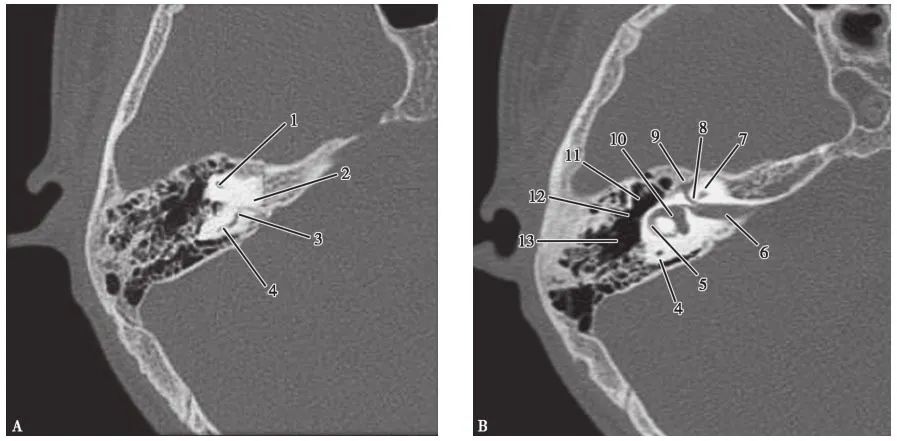

(CT矢状面)

A.耳蜗层面;B.前庭层面;C.面神经管乳突段层面1.颈静脉球;2.内耳道;3.耳蜗;4.前庭导水管;5.后骨半规管;6.总骨脚;7.上骨半规管;8.前庭;9.面神经管迷路段;10.鼓膜张肌;11.圆窗;12.外骨半规管;13.砧骨长脚;14.锤骨颈;15.面神经管乳突段